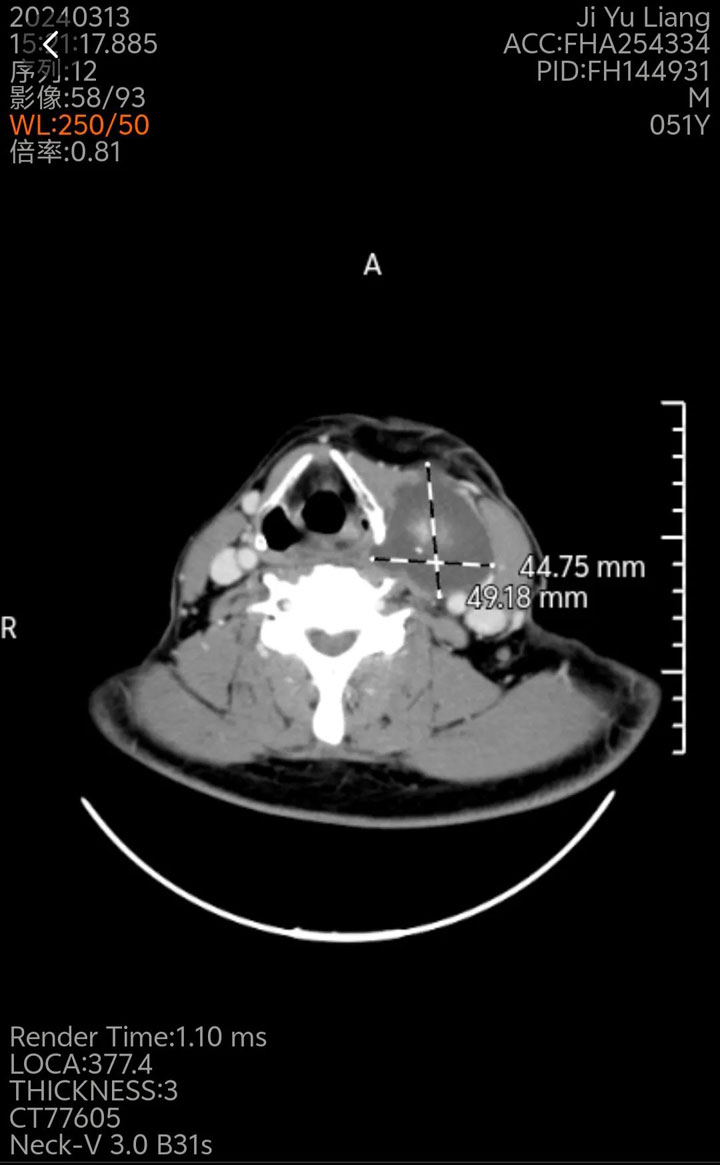

据了解,家住凤台的姬先生4个月前发现自己脖子有肿块,且出现了吞咽困难的情况,便到家门口的淮南东方医院集团凤凰医院就诊。入院后,经甲状腺彩超显示:患者甲状腺双侧叶多发结节伴钙化,TI-RADS 4类;甲状腺左叶和甲状腺偏右囊TI-RADS 3类;甲状腺左叶钙化灶,双侧颈部淋巴结;左侧颈部包块伴钙化,考虑患者可能是甲状腺恶性肿瘤。后行细针穿刺提示:患者为双侧甲状腺癌伴左侧颈部淋巴结转移。面对这样的病症,医生告诉他必须尽快采取手术治疗。

姬先生得知这一沉重的消息倍感焦虑和无助,便向医生求助。在医生的建议下,姬先生决定在东方总院手术。来到总院,孟院长仔细查看了他的病例,由于患者左侧颈部淋巴结转移多,病灶大,且左侧梨状窝及会厌溪受压,不排除侵犯可能;同时术后可能还出现梨状窝瘘等并发症,这也导致手术的难度风险增大,详细评估患者情况后,孟院长邀请了医院超声科、影像科、麻醉科等开展了MDT(多学科会诊),共同为姬先生协助制定手术方案,准备对患者行“甲状腺癌联合根治术(甲状腺全切+左侧根治性颈淋巴结清扫术)”。